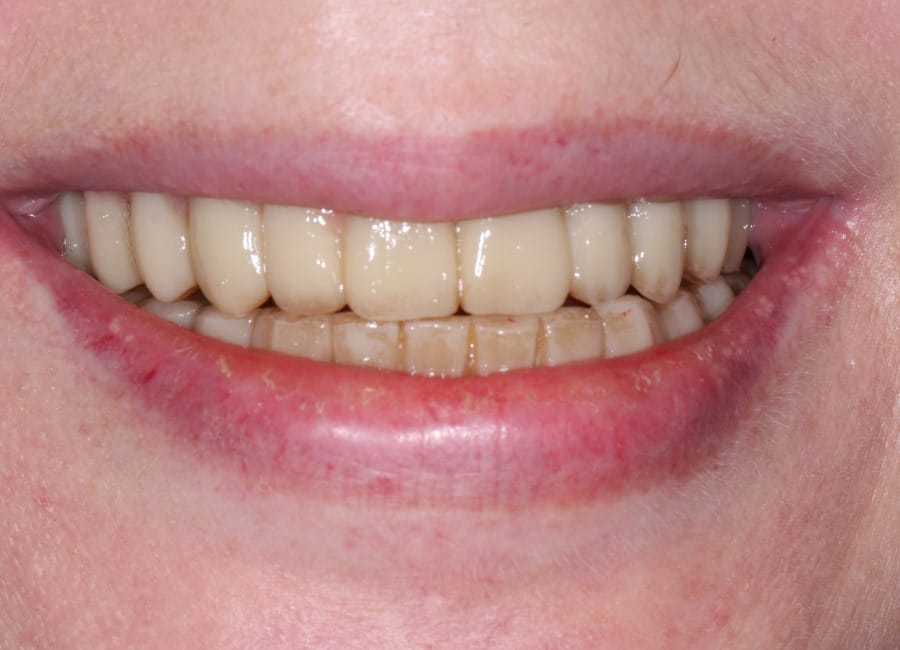

The moment Natalie saw her new smile, the emotion was undeniable. What had once been a source of discomfort, anxiety, and embarrassment had been completely transformed. Her new teeth restored full function and aesthetics, giving her back the ability to eat, speak, and smile without hesitation.

This result was more than cosmetic. It marked the end of a long journey filled with fear and hesitation, and the beginning of a new chapter defined by confidence and well-being. Natalie’s story is a powerful example of how modern dentistry, when led by skilled professionals and supported by cutting-edge technology, can restore much more than teeth.

My first look in the mirror with my new set of teeth was incredible. I’m in disbelief and I feel a bit overwhelmed because it looks so good. At the same time, it looks so natural, it is the shape of my natural teeth and smile. They feel comfortable, I can speak with them. I feel very confident that this will work very well for me.